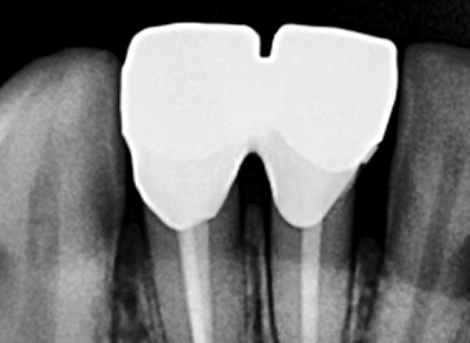

Cleaning & Filling

Sealing the Canal

Restoration